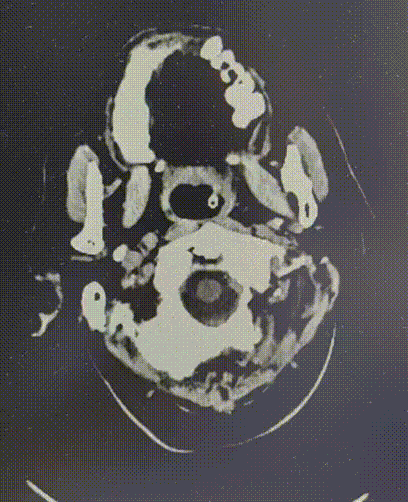

6月24日

DWI提示右侧半球多发点状新发梗死。